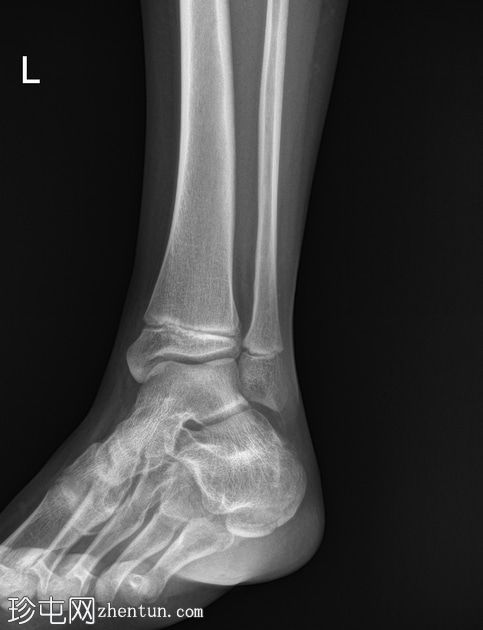

X线片

侧位片

双侧跟骨密度增高,可见跟骨骨骺碎片,提示跟骨骨骺炎,又称塞弗氏病。

塞弗氏病,又称跟骨骨骺炎,是生长发育期儿童足跟(或跟骨)生长板后方的炎症。

该病被认为是由足跟反复受力引起的。这种疾病良性且常见,通常在生长板闭合后或活动量减少时缓解。